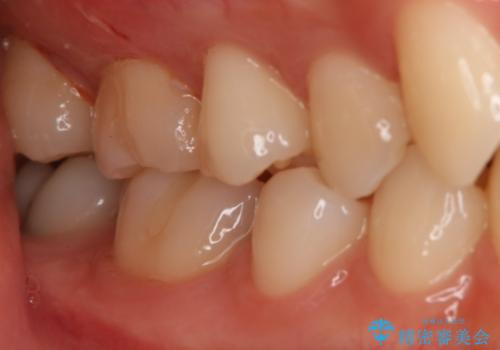

- 右上6番の保険材料で詰められた部分をセラミックにやり変え希望の患者様です。

切削量などを考慮し、セラミックインレーでの治療を選択しました。

う蝕が深くまで進行していたので、全て除去した上でCR裏層を行い形成、印象を行っています。